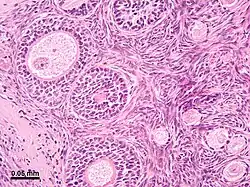

The surface of the ovaries is covered with a membrane consisting of a lining of simple cuboidal-to-columnar shaped mesothelium,[7] called the germinal epithelium.

The outer layer is the ovarian cortex, consisting of ovarian follicles and stroma in between them. Included in the follicles are the cumulus oophorus, membrana granulosa (and the granulosa cells inside it), corona radiata, zona pellucida, and primary oocyte. Theca of follicle, antrum and liquor folliculi are also contained in the follicle. Also in the cortex is the corpus luteum derived from the follicles. The innermost layer is the ovarian medulla.[8] It can be hard to distinguish between the cortex and medulla, but follicles are usually not found in the medulla.

Follicular cells are flat epithelial cells that originate from surface epithelium covering the ovary. They are surrounded by granulosa cells that have changed from flat to cuboidal and proliferated to produce a stratified epithelium.